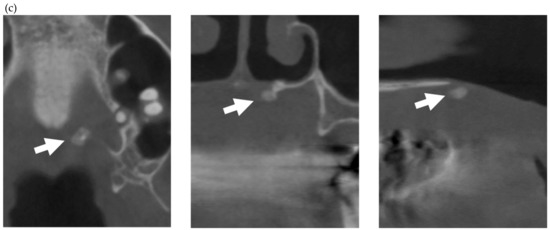

Figure 2.

Multiple external root resorption and calcinosis at the oral region in pt. 3. A dental X-ray photo and CBCT image of teeth (a,b) and the deposition of calcinosis at the nasal spur (c). The white arrowhead points to root resorption, the black arrowhead to PDL space widening, the white arrow at calcinosis and the black arrow indicates the failure to close the space with orthodontic treatment.

In the present study, MERR was detected in four SSc patients, including one described in a case report (pt. 1) [12]. The causes of external resorption, including trauma, periodontal and periapical inflammation, orthodontic treatment, internal bleaching or tumors, were not found in the teeth having external resorption. Dental X-rays and CBCT images showed that MERR was observed in six, six, and four teeth in pts. 2, 3, and 4, respectively (Figure 1a, Figure 2a and Figure 3a). A widening PDL space was detected in all patients. A space between canines and premolars in the upper jaw was found in pts. 3 and 4 (Figure 2a and Figure 3a). Furthermore, the deposition of calcinosis in the nasal spur was noted in pts. 1, [12], 2, and 3, while calcinosis in the palatal plate was observed in pt. 4 (Figure 2c and Figure 3c).